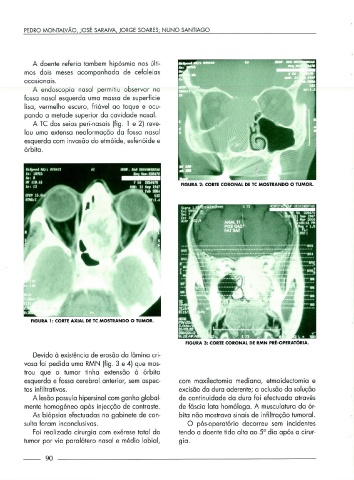

A TC dos seios peri-nasais (fig. 1 e 2) reve-

lou uma extensa neoformação da fossa nasal

esquerda com invasão do etmóide, esfenóide e

órbita.

FIGURA 2: CORTE CORONAL DE TC MOSTRANDO O TUMOR.

FIGURA 1: CORTE AXIAL DE TC MOSTRANDO O TUMOR.

FIGURA 3: CORTE CORONAL DE RMN PRÉ-OPERATÓRIA.

Devido à existência de erosão da lâmina cri-

vasa foi pedida uma RMN (fig. 3 e 4) que mos-

trou que o tumor tinha extensão à órbita

esquerda e fossa cerebral anterior, sem aspec- com maxilectomia mediana, etmoidectomia e

tos infiltrativos. excisão da dura aderente; a oclusão da solução

A lesão possuía hipersinal com ganho global- de continuidade da dura foi efectuada através

mente homogéneo após injecção de contraste. de fáscia lata homóloga. A musculatura da ór-